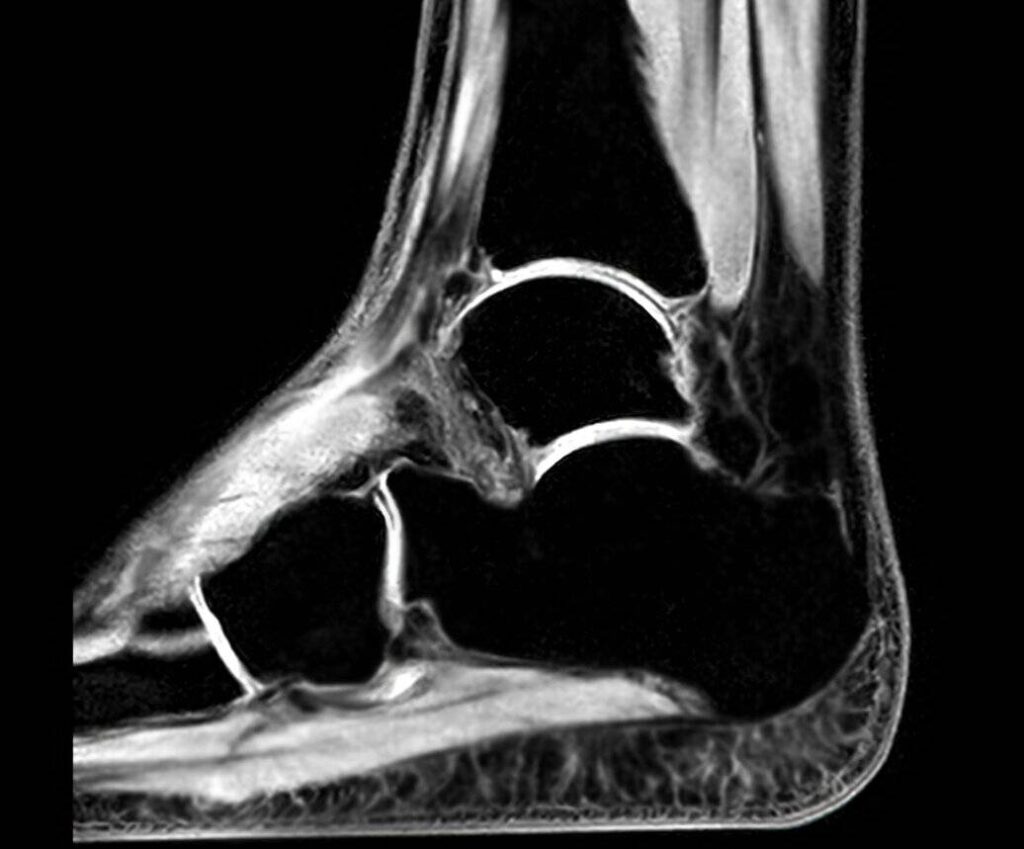

MRT Sprunggelenk oder CT Sprunggelenk?

- Die MRT (Magnetresonanztomographie) ist ideal zur Darstellung von Weichteilen, wie Bändern und Sehnen, ohne Strahlenbelastung.

- In einigen Fällen werden sowohl MRT als auch CT eingesetzt, um ein umfassendes Bild des Sprunggelenks zu erhalten.